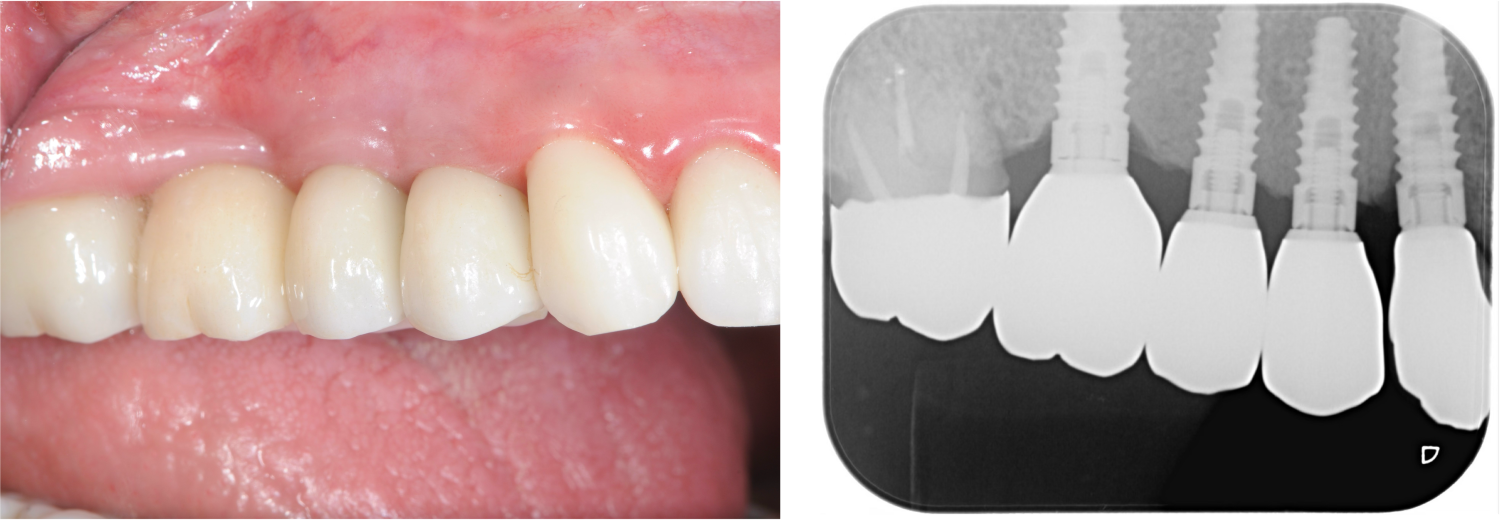

多数歯欠損のインプラント治療の症例(うえだ歯科)

| 治療内容 | 歯周病で骨の吸収が重度で保存不能なため抜歯、仮の入れ歯を作り、6ヶ月の抜歯窩の治療の後に、インプラントのCTによる診査診断を行い、下顎に6本インプラント埋入と同時に仮歯を入れる。その後、上顎は8本のインプラント埋入と同時に仮歯を入れる。左右上6はソケットリフトによる上顎洞拳上術を行う。その後免荷期間6ヶ月待ってセラミックを用いた上部構造作製、装着しメンテナンスに移行する。 |